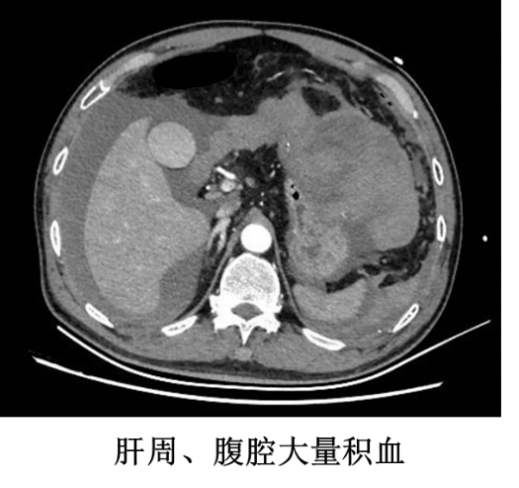

接到电话后,王恺立即安排科室同事做好接诊准备,并积极完善术前准备工作。根据患者家属描述,患者 2 天前突发腹痛,于当地医院行腹部 CT 检查提示肝癌破裂出血,并于当日在兄弟医院行急诊肝动脉栓塞术止血。术后第二天,患者诉腹部疼痛症状加重,复查血常规见血红蛋白仍呈下降趋势,血压下降、心率加快,提示仍有活动性出血并失血性休克。患者由急诊 120 转运至南昌大学第二附属医院急诊抢救室后,医院立即予以积极抗休克治疗,并迅速完成腹部增强 CT 检查,证实肝癌破裂出血并腹腔大量积血,估算出血量超过 2500 ml。

根据患者治疗病史、当前临床表现及影像学分析,患者的肿瘤位于左肝外叶,外生性生长,血供丰富,肝动脉栓塞后止血效果不佳。